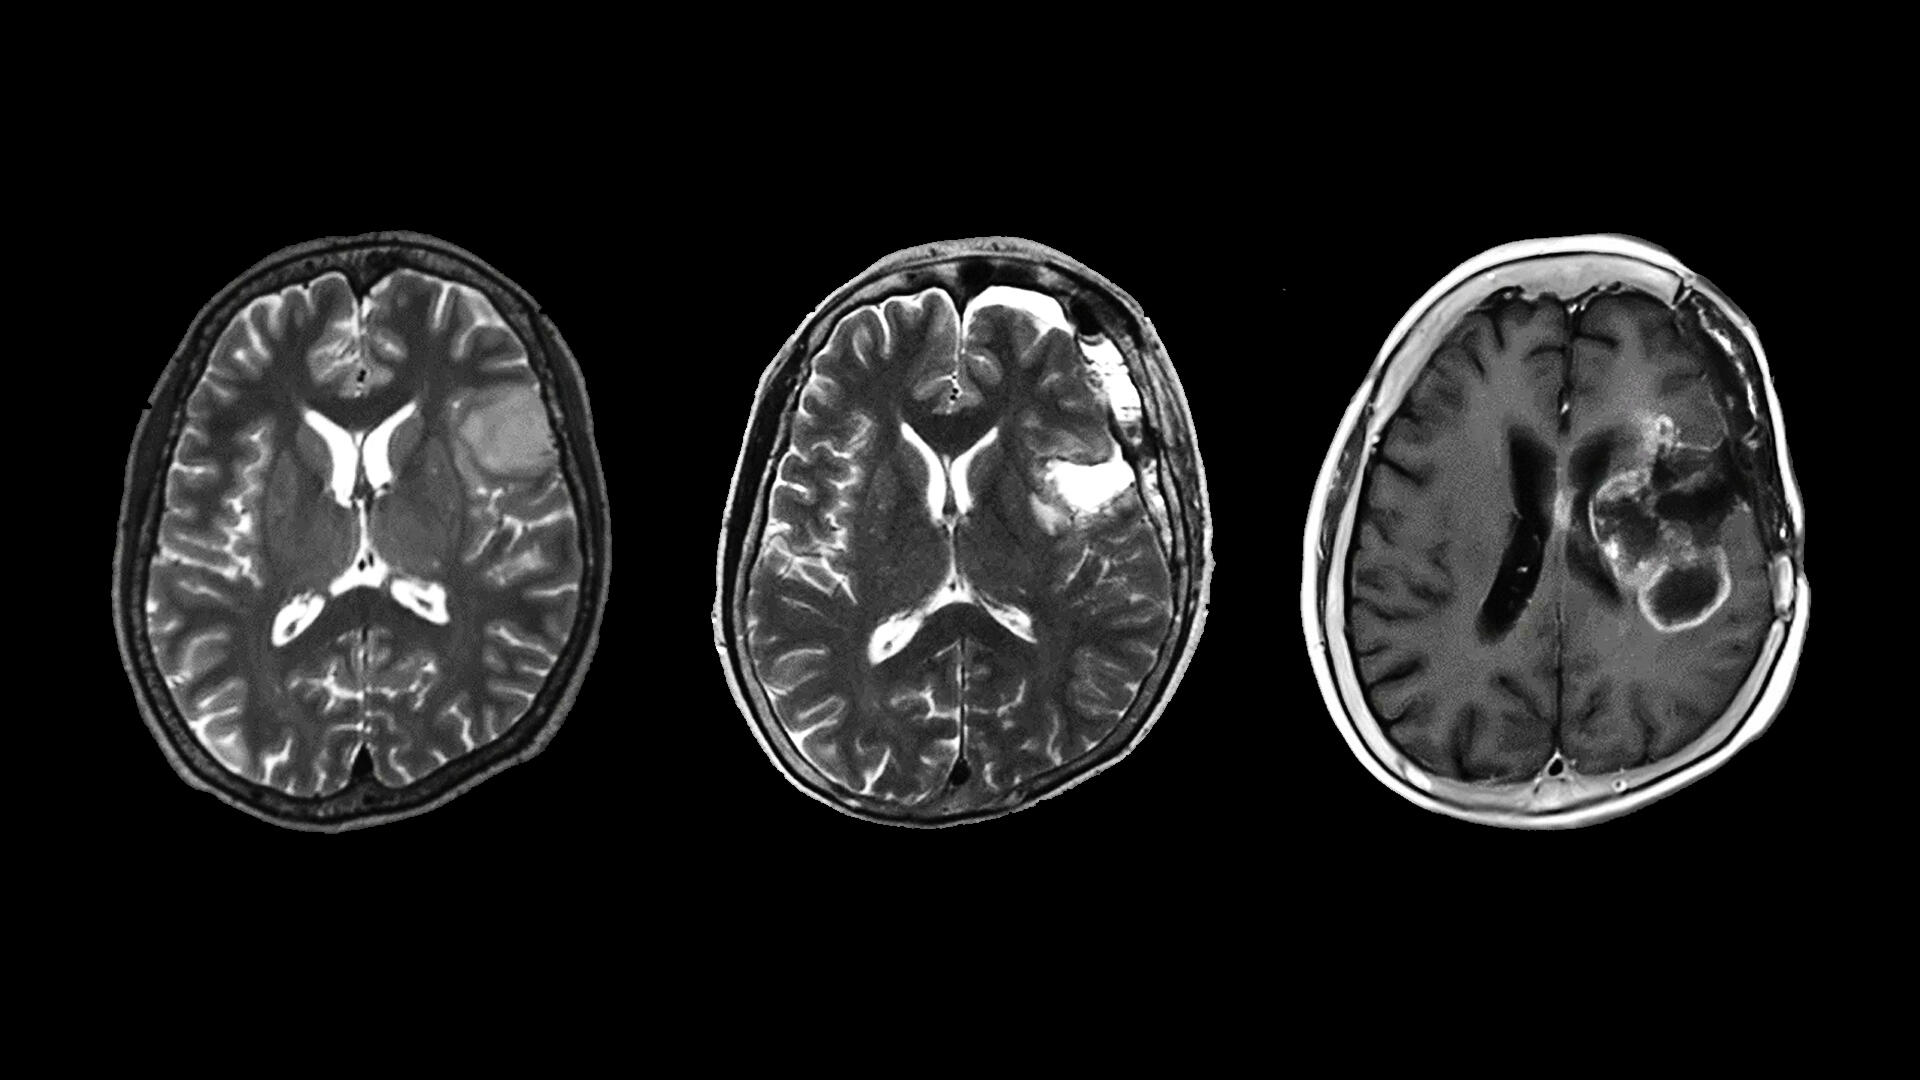

The Nagoya University research team, led by Yuji Kibe and Kazuya Motomura of the Department of Neurosurgery, analyzed localized IDHwt astrocytomas and found that all resulted in malignant recurrence and a poor clinical prognosis similar to that of glioblastomas. Glioblastomas are among the most malignant tumors, with an average survival time of 8 months and less than 7% of patients survive for five years.

Motomura believes that the findings of the group are important for doctors and patients. “All tumors that we investigated had a dismal prognosis despite multidisciplinary treatment,” he said. “For patients with gliomas, our research results should lead patients to receive the proper clinical diagnosis and treatment. For physicians, IDHwt astrocytomas must be followed with great caution, even after total removal. Strong postoperative therapy should be considered. As almost all patients with diffuse astrocytomas present with radiographic imaging findings suggesting a localized tumor mass, physicians may misdiagnose the patient with a low-grade tumor instead of a malignant tumor; therefore, our findings suggest physicians should consider the possibility of such tumors.”